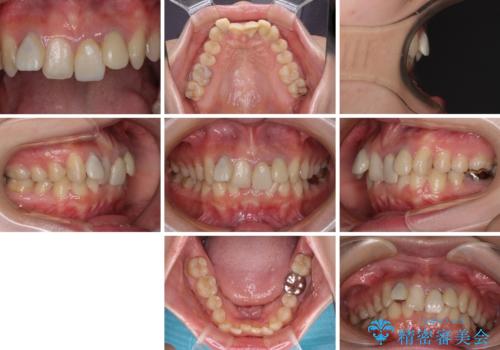

- 前歯のデコボコと、その結果むし歯が進行していることを気にして来院された患者様です。

前歯や奥歯の根管治療を行い、その後上下左右の第一小臼歯4本を抜歯してワイヤー装置にて矯正治療を行うこととしました。

矯正治療後には、根管治療を行った歯をオールセラミッククラウンにて補綴治療を行うこととしました。